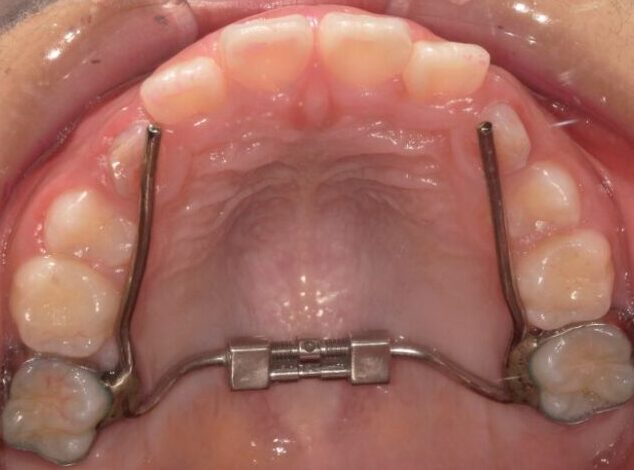

床矯正

(しょうきょうせい)顎の幅や大きさをコントロールするために使用する、取り外し式の装置です。歯を直接大きく動かすのではなく、顎の骨を少しずつ広げることで、永久歯が並ぶスペースを確保します。

固定式拡大装置

顎の幅や形を整えるために、歯に直接固定して使用する装置です。取り外し式の床矯正よりも安定性が高く、確実に顎を広げたい場合に用いられます。